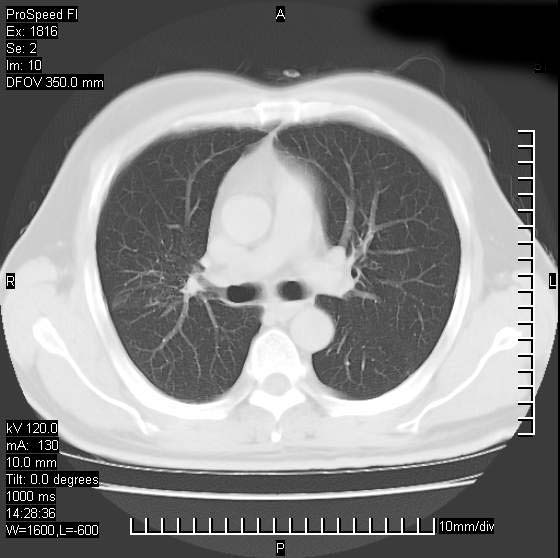

男性,50 ,肺结核9年,咳嗽,胸痛一周。右上肺见一厚壁空洞,周边有点样钙化,胸膜牵拉,洞壁较光整。诊断结核性空洞。有癌性的可能吗? 余肺野无异常,没有上传。

洞壁较厚内壁比较光整,两个病灶有关联性,纵隔淋巴结不大,考虑结核性空洞。

部分层面见空洞为近似新月形,洞壁内缘尚规整且近肺门侧,周围见索条影、卫星灶,结合病史,首先考虑肺tb可能大。

右肺上叶为两个病灶,前面为陈旧型结核灶,其后方病灶像肺脓肿

结核空洞并结核复发可能性大。

同意空洞型结核诊断,不过要注意随访复查。或与旧片比较。

支持继发型结核伴空洞形成.